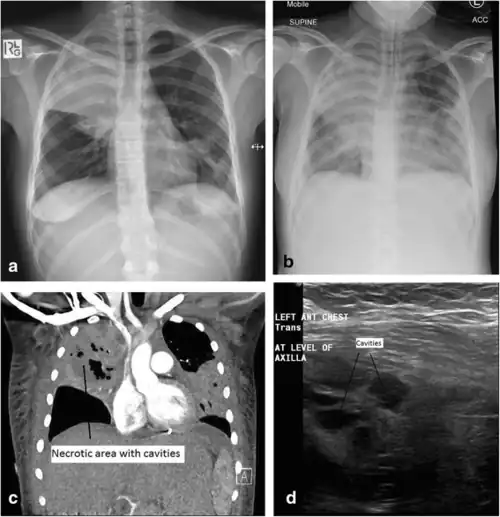

a) Initial plain chest radiograph showing a dense right upper zone airspace opacity and lingula airspace changes, consistent with multi-focal pneumonia. The following images were performed 24 h later. b) Plain chest radiograph with the patient intubated and ventilated revealing cavitation in the right mid to upper zones, pleural effusion and more general airspace changes bilaterally. c) Computed tomography (CT) scan, coronal view, demonstrating non-enhancing area (necrotic) thin-walled cavities within the right upper lobe and lingula. d) Lung ultrasonographic image displaying thin-walled cavities in the lingula region of the left lung. This requires further clarification.[note 1]